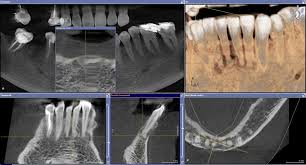

Difficulties In The Diagnosis Of Periapical Translucencies And In The Classification Of Cemento Osseous Dysplasia Bmc Oral Health Full Text

Difficulties In The Diagnosis Of Periapical Translucencies And In The Classification Of Cemento Osseous Dysplasia Bmc Oral Health Full Text from media.springernature.com